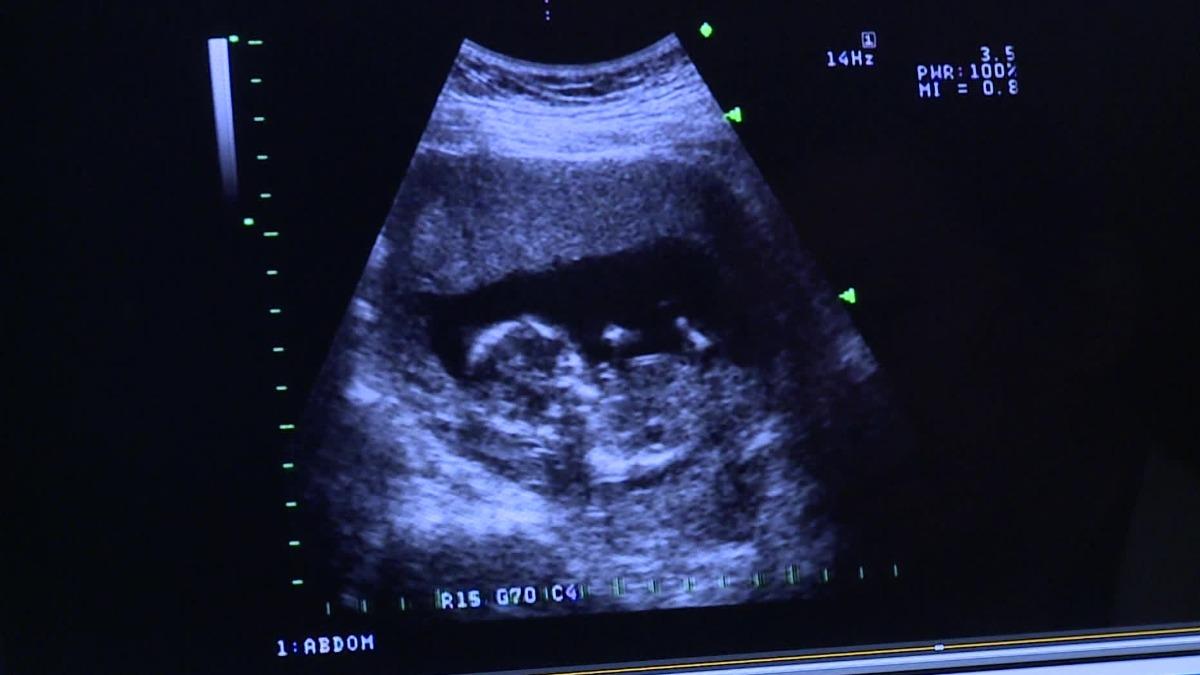

What exactly is surrogacy? It is an arrangement in which a woman agrees to carry a child that will then legally belong to someone else after birth. Often, the intended mother or another woman provides the egg, rather than the surrogate. The practice is highly controversial, which is why it is only legal in 12 countries.

A major reason for this hesitation to legalize surrogacy is that no matter who provides the genetic material or the state of local healthcare, being pregnant and giving birth remains a highly risky medical procedure. Hemorrhages, hypertension, and postpartum depression can happen to anyone giving birth, not to mention death. Some doctors consider it medically unethical for this reason.